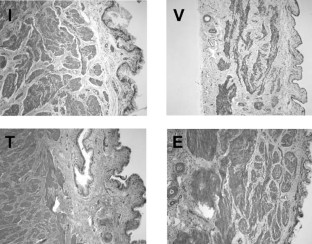

The role of steroid hormones in regulating vaginal smooth muscle contractility was investigated. Rabbits were kept intact or ovariectomized. After 2 weeks, animals were continuously infused with vehicle or supraphysiological levels of testosterone (100 μg/day), or estradiol (200 μg/day), for an additional 2 weeks. The distal vaginal tissue was used to assess contractility in organ baths and changes in tissue structure were assessed by histology. Ovariectomized animals infused with vehicle exhibited significant atrophy of the muscularis and decreased epithelial height, resulting in thinning of the vaginal wall. Estradiol infusion increased epithelial height, comparable to that of intact animals, but only partially restored the muscularis layer. In contrast, testosterone infusion completely restored the muscularis layer, but only partially restored the epithelial height. In vaginal tissue strips contracted with norepinephrine and treated with bretylium, electrical field stimulation (EFS) caused frequency-dependent relaxation that was slightly attenuated with vehicle, significantly inhibited with estradiol and significantly enhanced with testosterone. VIP-induced relaxation was slightly attenuated in tissues from vehicle and estradiol-infused groups, but was enhanced in tissues from testosterone-infused animals. Contraction elicited by EFS or exogenous norepinephrine was not significantly altered with ovariectomy or steroid hormone infusion when data were normalized to potassium contraction. However, the tissue from testosterone-infused animals developed significantly greater contractile force to norepinephrine. These observations suggest that steroid hormones may be important regulators of vaginal tissue structure and contractility.